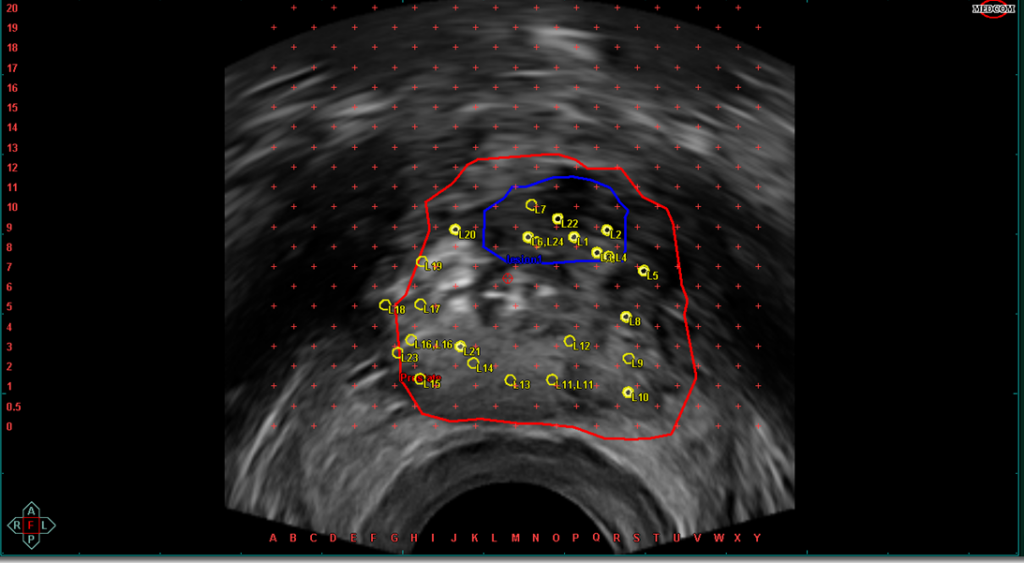

–Εν συνεχεία τοποθετείται το ειδικό υπερηχογράφημα στο ορθό (έντερο) και απεικονίζεται σε πραγματικό χρόνο ο προστάτης και γίνεται η σύντηξη των εικόνων της μαγνητικής με αυτές του υπερήχου. Παράλληλα σχεδιάζονται και προγραμματίζονται τα δείγματα που θα ληφθούν ώστε οι βιοψίες να είναι στοχευμένες και με μεγάλη ακρίβεια να εξασφαλισθεί η λήψη βιοψιών από τις ύποπτες περιοχές. (Βλέπε Εικόνα 7)

Εικόνα 7: Εικόνα υπερήχου του προστάτη που έχει γίνει σχεδιασμός του προστάτη και τις βλάβης ενώ έχουν σχεδιαστεί και προγραμματιστεί τα δείγματα που θα ληφθούν, που είναι στοχευμένα και κατευθυνόμενα.

-Εν συνεχεία λαμβάνονται τα δείγματα των βιοψιών. Για την λήψη των δειγμάτων με ακρίβεια χιλιοστού στο περίνεο εξωτερικά τοποθετείται ειδικός πίνακας συντεταγμένων (Αγγλική Ονομασία Grid).Ο πίνακας αυτός είναι σε πλήρη συμφωνία με το λογισμικό και την σχεδίαση του προστάτη και των βλαβών με αποτέλεσμα ο Ουρολόγος να τοποθετεί την βελόνα λήψης βιοψιών με βάση τις οδηγίες του λογισμικού σε συγκεκριμένο σημείο που ανταποκρίνεται στην πράξη ακριβώς σε αυτό το σημείο του προστάτη στο σώμα του ασθενή.(Βλέπε Εικόνες 8 & 9) (Βίντεο 1)

Εικόνα 8: Πίνακας συντεταγμένων με γράμματα και αριθμούς που τοποθετείται στο περίνεο σε συμφωνία με τις εικόνες του υπερήχου και της μαγνητικής και στον οποίο ο ουρολόγος τοποθετεί με ακρίβεια χιλιοστού την βελόνα βιοψίας με βάση τον σχεδιασμό της βλάβης που έχει κάνει και τις οδηγίες του ειδικού λογισμικού που κατευθύνει την λήψη των δειγμάτων.